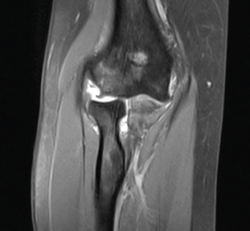

En las imágenes de RM podemos ver los signos de arrancamiento de la inserción proximal de ligamento colateral lateral, importante cantidad de derrame articular y el edema óseo localizado en toda la parte medial del humero distal y del cúbito y el radio proximales (Figura 5).

Figura 5. Imagen coronal de resonancia magnética del codo izquierdo, realizada a las 3 semanas de la lesión. Observamos la avulsión proximal del ligamento colateral lateral, la subluxación de la cabeza radial y el edema óseo.